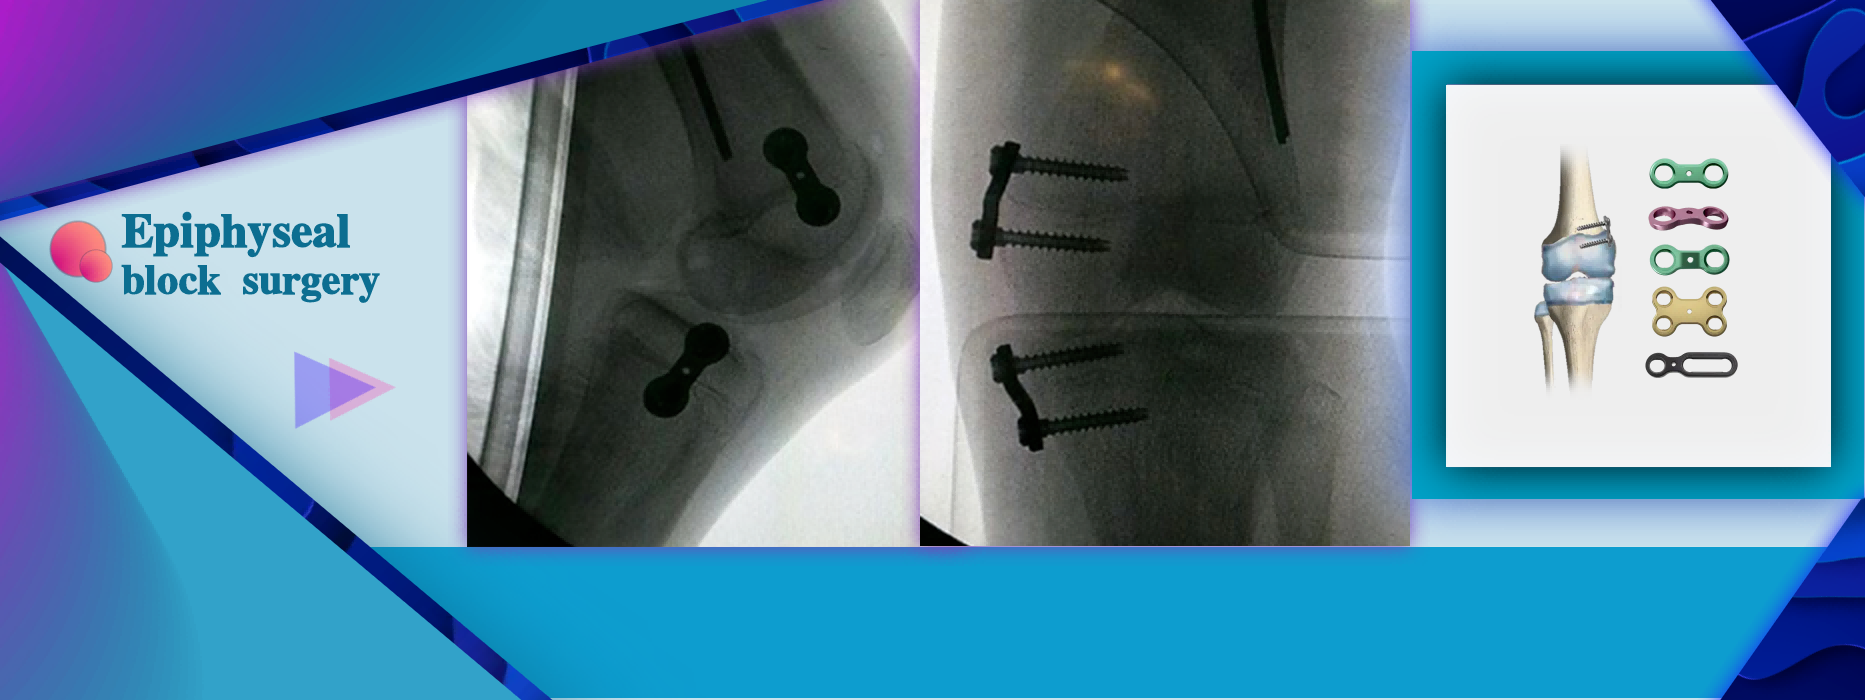

More InformationLimb angular deformity and the need for correction during the growth period of children.

Limb angular deformity and the need for correction during the growth period of children.